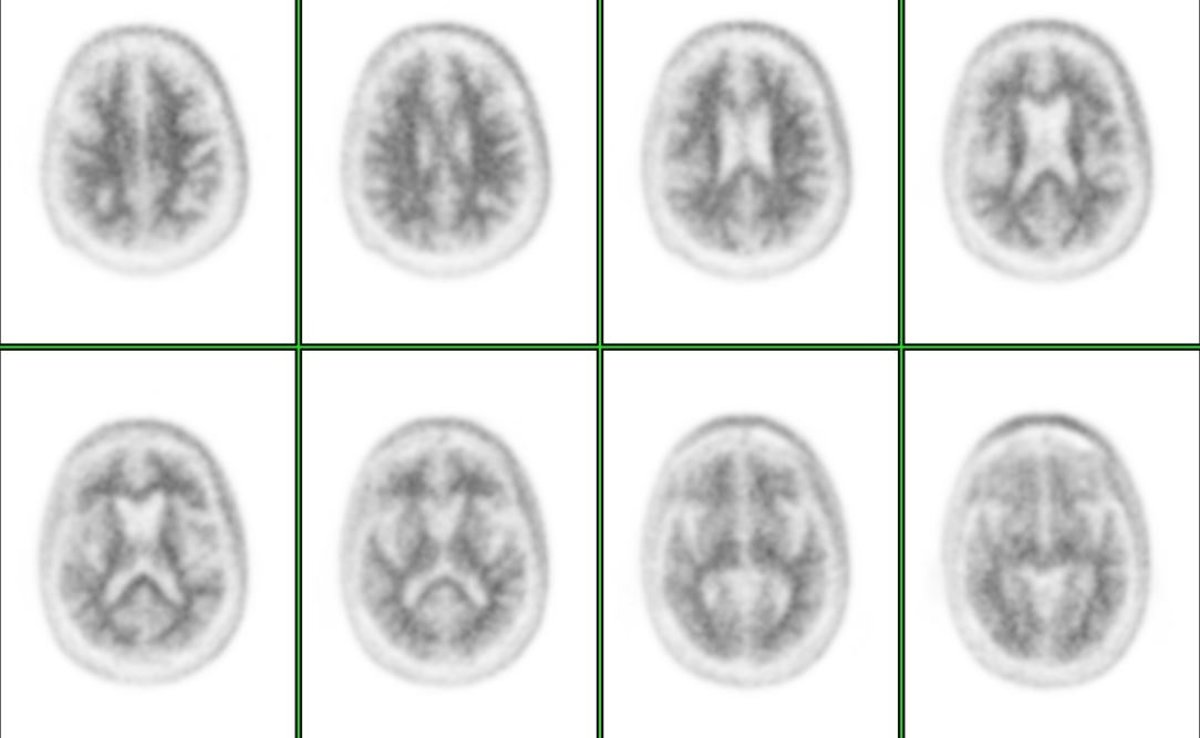

Esta prueba supuso una revolución diagnóstica en torno a la enfermedad de alzhéimer pues, hasta entonces, los distintos estudios diagnósticos de imagen RM y TAC desvelaban la muerte neuronal o la pérdida de volumen. "Antes que se produzca esta pérdida de volumen, hay una disfunción neuronal que los estudios PET con fluorodesoxiglucosa permiten evaluar. "Pero, incluso antes de la disfunción neuronal, se produce en el cerebro un depósito de las placas de amiloide, que puede ser estudiado con PET", ha precisado el doctor Pablo Sopena.

La PET de amiloide se convertía así en la primera y única herramienta diagnóstica aprobada por la Unión Europea que muestra la presencia o ausencia de placas amiloides, lo que suponía una "auténtica revolución diagnóstica" en torno al alzhéimer.